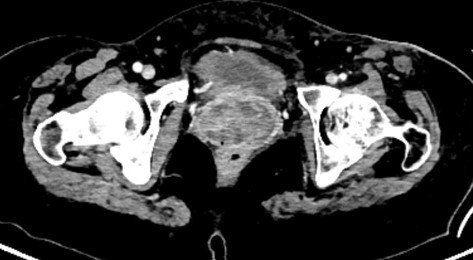

Արգանդի մարմնի քաղցկեղի IV փուլում գտնվող 42-ամյա կինը սկսել է բուժումը ՈՒԱԿ պալիատիվ ծառայության կլինիկայում՝ գանգատվելով սեռական ուղիներից առատ արյունային արտադրությունից: Անհրաժեշտ հետազոտություններից հետո տեղափոխվել է ներխոռոչային և ներհյուսվածքայի ճառագայթային թերապիայի բաժանմունք: Կյանքի ցուցումներով իրականացվել է բրախիթերապիա՝ արյունահոսությունը կանգնեցնելու նպատակով:

Երեք շաբաթ տևած բուժման արդյունքում դադարել է արյունահոսությունը, տեղի է ունեցել ուռուցքի հետաճ՝ բարելավելով պացիենտի կյանքի որակը և հնարավորություն ստեղծելով շարունակելու բուժումը: